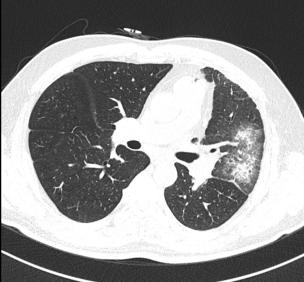

患者,女,49岁,既往无吸烟史;CT发现双肺小结节1年,为进一步明确诊断进行薄层CT扫描并将影像学资料交与AI进行进一步判定。

AI判读发现患者右上肺有10.8*8.5 mm结节,且在左肺见7.2*5.3 mm结节。两结节均呈现空泡征且有新生血管生成,左肺结节更是存在分叶征。

最初发现右肺结节时,由于结节较小判读比较困难,医生并没有给出明确诊断而时嘱托患者继续随访。本次患者影像学经AI评估,认为患者右上肺结节可能高度恶性可疑,左下肺结节恶性风险稍低但依然存在。